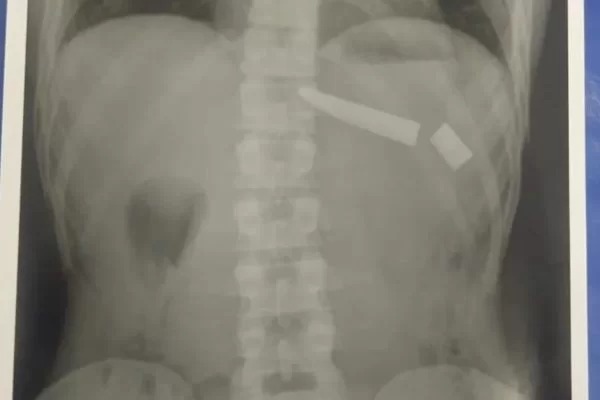

A Polícia explica que os dois homens começaram a brigar. Logo após, o suspeito esfaqueou a vítima na região dos rins e nas costas, fazendo com que a faca quebrasse em dois lugares do tórax.

Durante o desentendimento os envolvidos chegaram a “rolar no chão” e a vítima, mesmo atingida, conseguiu correr e pedir ajuda.